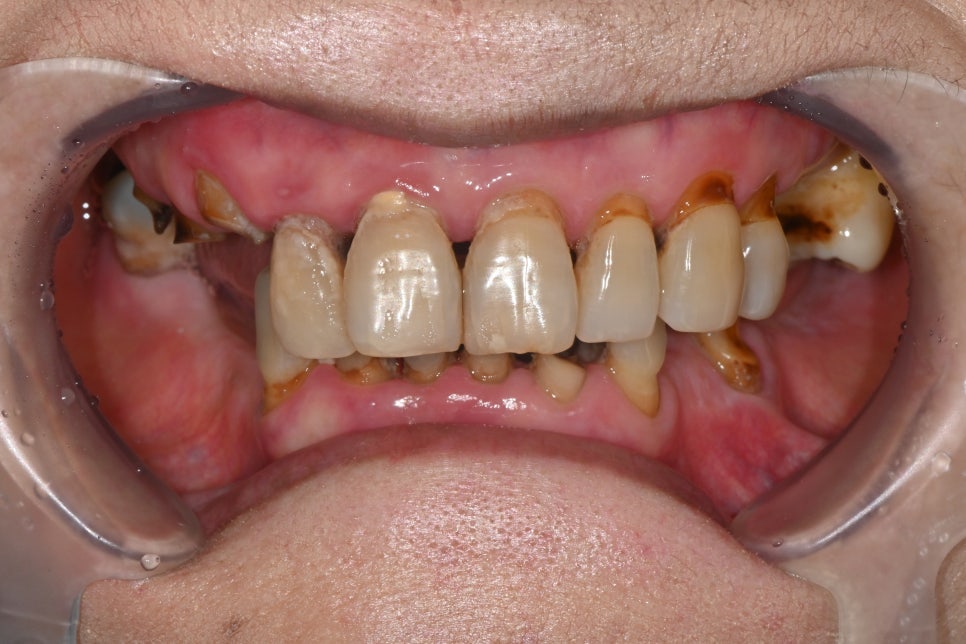

환자분은 30년 이상 치과 진료를 미루며

전체적인 치아 마모, 탈락, 잇몸 염증이

복합적으로 진행된 상태였습니다.

특히 어금니가 거의 모두 빠져 있어

저작 기능이 상실된 상황이었고

남아 있는 치아들도 마모가 심해 교합을

유지하기 어려웠습니다.

잇몸 사이에는 음식물이 끼면서

염증과 냄새가 반복적으로 발생했고

일상적인 식사에도 많은 불편이 있었습니다.